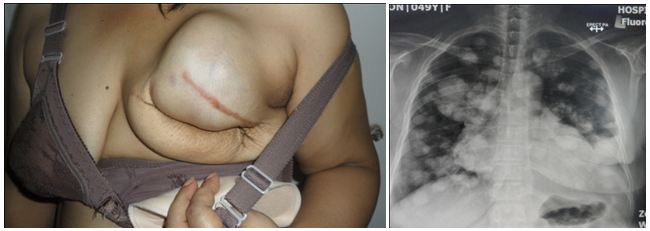

Two weeks ago, I posted the story of Rose, a 49-year-old Indonesian lady who had a big lump in her breast. She underwent surgery twice because the lump kept recurring. Then the non-cancerous massed turned cancerous. It spread to her lungs.

Rose was told to go for chemotherapy. She refused and came to seek out help.

Two weeks on our therapy, Rose got better. Listen to what her husband told us.

1. The swelling of her hands and feet subsided.

2. She can now stand up without difficulty and can walk around the house compound. This is something that she could not do earlier. Also before the herbs, she would feel breathless and sweat a lot even with a little bit of movement. All these are gone!

3. Her appetite has improved.

4. Her cough with itchy throat was gone.

5. Her sleep has improved.